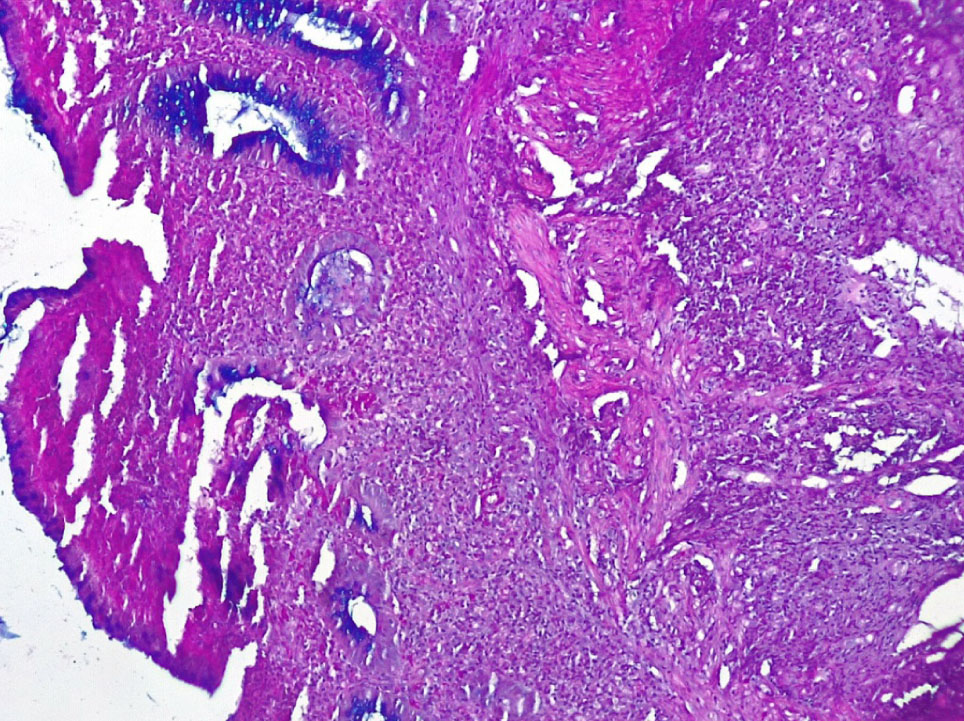

Окраска на слизь выявила почти полное исчезновение слизи на поверхности цилиндрического эпителия СО и в большинстве крипт за счет резко выраженной атрофии бокаловидных клеток (не более 4–5 БК на крипту) (+++) (рис. 5).

Рис. 5. Основная группа: снижение секреции муцина цилиндрическим эпителием СО толстой кишки, атрофия бокаловидных клеток и небольшое количество альциан + слизи в криптах. ШИК-реакция с докраской альциановым синим, ×200

В отдельных участках СО при НЯК встречались единичные крипты, содержащие отдельные бокаловидные клетки и альциан + гликопротеиды (нейтральные мукополисахариды), резко выраженное хроническое воспаление стромы с развитием рыхлой волокнистой соединительной ткани (фиброза) (+++ степень атрофии и фиброза) (рис. 6).

Рис. 6. Основная группа: в СО при НЯК отмечается резкая атрофия крипт и бокаловидных клеток, содержащих незначительное количество альциан + муцина. ШИК-реакция с докраской альциановым синим, ×200